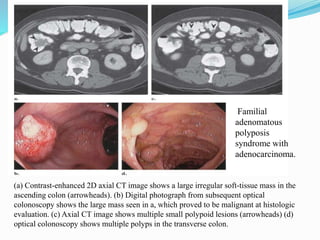

This document discusses colorectal polyps. It defines polyps and describes their types, including neoplastic and non-neoplastic polyps. It discusses adenomatous polyps in depth, noting their malignant potential increases with size over 1cm and villous architecture. Radiological diagnostic methods for polyps including single and double contrast barium enema and CT colonography are explained. The document provides an overview of polyp pathogenesis and genetic syndromes like FAP that increase cancer risk.